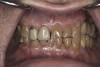

(6.) Preoperative right lateral, open view.

Figure 6

(7.) Preoperative anterior, open view. Note the significant amount of wear, erosion, and abfraction lesions.

Figure 7

(10.) Preoperative anterior, closed view. Note the end-to-end occlusion of the anterior teeth and the wear on the incisors and centrals resulting in no anterior or canine guidance.

Figure 10